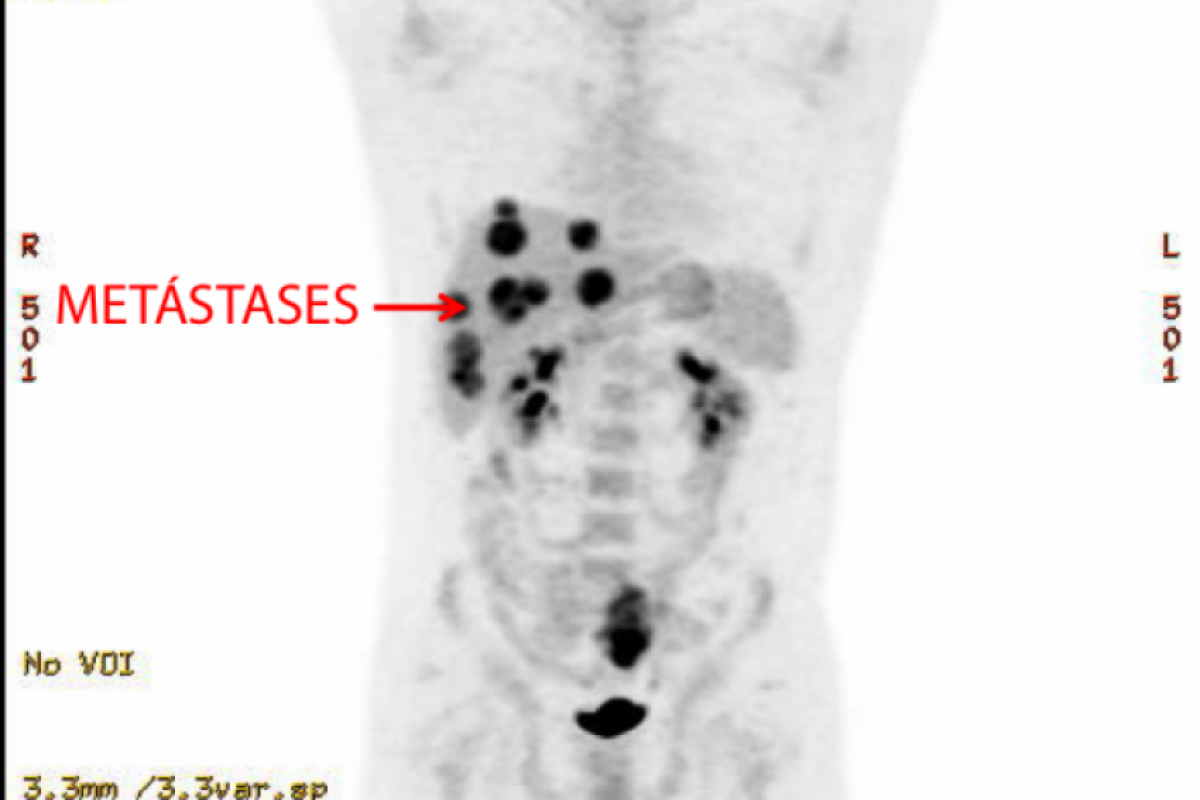

Geraldo Vaz Junior, de 58 anos, vive um drama médico e jurídico desde que recebeu um fígado com câncer no transplante realizado no Hospital Albert Einstein, em São Paulo, pelo SUS. O caso, considerado extremamente raro por especialistas, resultou em metástase no pulmão do paciente, confirmando que o tumor teve origem no órgão transplantado.

O laudo indicou cromossomos femininos (XX) nas células do tumor, enquanto Geraldo, homem cis, possui cromossomos XY: prova de que o câncer veio com o órgão. O paciente foi submetido a um segundo transplante em maio de 2024, mas, em agosto, foi diagnosticado com metástase pulmonar do mesmo tipo de adenocarcinoma.

Sem possibilidade de cura, o paulista enfrenta agora tratamento com quimioterapia contínua, enquanto tenta obter respostas sobre como um órgão com câncer foi aprovado para transplante.